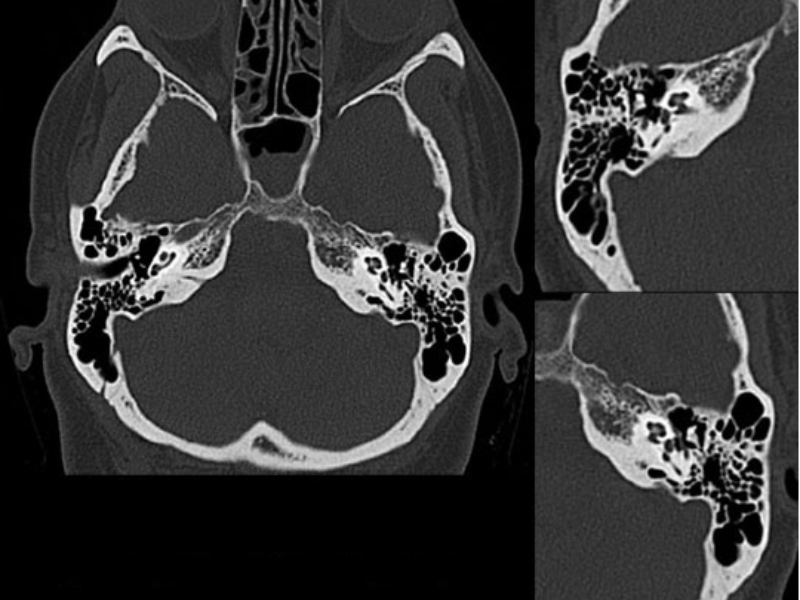

Fine details of inner ear revealed with high spatial resolution

With a o.5 mm collimation,finer structures are better visualized with every scan. A 1024*1024 reconstruction matrix enhances the spatial resolution and helps reveal the details for the most challenging examinations.